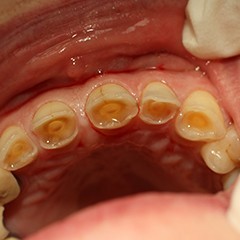

Abrasion is the abnormal wear of a tooth. It is usually caused by toothpaste which is too abrasive (gritty). Abrasion exposes the nerve endings in the dentine and the tooth becomes sensitive to hot and cold. Emergency Dental Service provides 24-hour emergency patient support to take care of your emergency dental problems. If you have any dental emergency in Upper Darby, contact us at 215-622-9864.